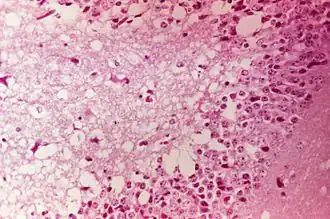

A l'autopsie, on peut constater des lésions septicémiques (congestion, hémorragies) accompagnées ou non d'une entérite. Au laboratoire, on détecte des lésions microscopiques nécrotiques et hémorragiques des centres nerveux.